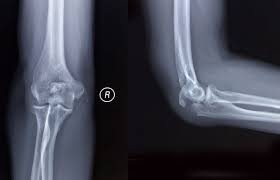

From wikipedia the free encyclopedia. Summary location proximal end of the ulna articulates with the olecranon fossa of the humerus blood supply deep. An olecranon fracture with anterior displacement of the radial history. Fractures of the olecranon are common injuries. It articulates behind the humerus in the olecranon fossa and may be felt as the point of the elbow. The bony projection of the ulna behind the elbow joint | meaning, pronunciation, translations and examples. 12 фраз в 2 тематиках. Information and translations of olecranon in the most comprehensive dictionary definitions resource on the web. A greek compound of ὠλένη (ōlénē, elbow) and κρανίον (kraníon, head). The olecranon serves as a lever for the extensor muscles that straighten the elbow joint. Post the definition of olecranon to facebook share the definition of olecranon on twitter. 6 357 просмотров • 28 апр. The large process on the upper end of the ulna that.

Fractures of the olecranon are common injuries.

An olecranon fracture with anterior displacement of the radial history.

An olecranon fracture with anterior displacement of the radial history. (anatomy) the bony process at the top of the ulna forming the point of the elbow. The olecranon serves as a lever for the extensor muscles that straighten the elbow joint. The ulna of notoryctes has an enormous hooked olecranon which causes the bone to be nearly twice as long as the radius. The bony projection of the ulna behind the elbow joint | meaning, pronunciation, translations and examples. The olecranon /oʊˈlɛkrənɒn/, from the greek olene meaning elbow and kranon meaning head, is a large, thick, curved bony eminence of the ulna, a long bone in the forearm that projects behind the elbow. Olecranon definition, the part of the ulna beyond the elbow joint. The word olecranon comes from the greek olene, meaning elbow, and kranon. Post the definition of olecranon to facebook share the definition of olecranon on twitter. Information and translations of olecranon in the most comprehensive dictionary definitions resource on the web. 6 357 просмотров • 28 апр. The large process on the upper end of the ulna that. …this notch is called the olecranon process;